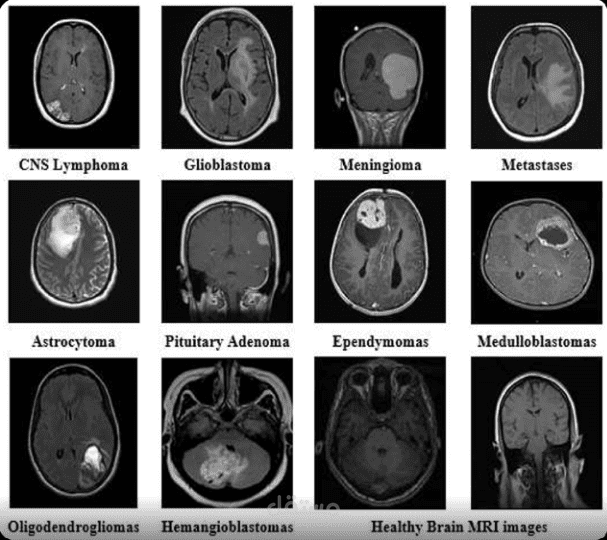

تصنيف أورام الدماغ بالذكاء الاصطناعي من صور MRI